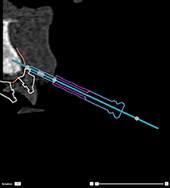

Correct |

|